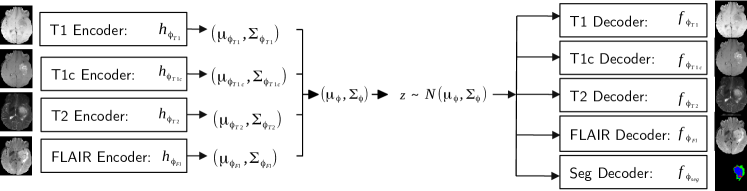

In our scenario, the clinician provides a subset of imaging modalities with some subsets of input modalities being more likely to be provided than others. We use an encoder-decoder to produce the missing modalities as well as the tumour segmentation. Although segmentation could be considered as a missing modality, we chose not to encode it as it is not observed in practice. Consequently, our model is composed of 4 encoders and 5 decoders (see Fig. 1).

We propose to use a multi-level latent variable to generate them. Figure 2 shows our network architecture. Unlike the existing hierarchical VAE models [11, 14], we propose a fully convolutional network. Each modality is independently encoded which produces 4 multi-scale means and variances . At each level, the means and the variances of the modalities present in the input subset are combined via the product of Gaussian defined in (4). We then decode the multi-scale latent variable for each of the modalities and the segmentation. Consequently, we have encoders and decoders. We assert that it is the first deep network which allows for missing modalities and performs 3D imaging reconstruction and segmentation in a variational manner.